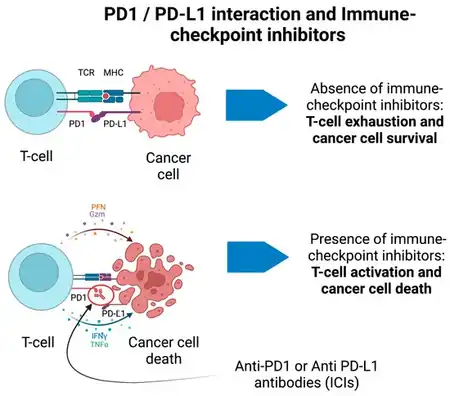

Paraneoplastic neurological syndromes may be related immune checkpoint inhibitors (ICIs), one of the underlying causes in inflammatory central nervous system diseases (CNS). The central idea around such research pinpoints treatment strategies to combat cancer related outcomes in the clinical arena, specifically ICIs. Research suggests that patients who are treated with ICIs are more susceptible to CNS disease (since the mechanism of ICIs induces adverse effects on the CNS due to augmented immune responses and neurotoxicity).[26] The purpose of this exploration was to shed light on immunotherapies and distinguishing between neurotoxicity and brain metastasis in the early stages of treatment. In other research, scientists have found that paraneoplastic peripheral nerve disorders (autoantibodies linked to multifocal motor neuropathy) may provide important clinical manifestations.[27] This is especially important for patients who experience inflammatory neuropathies since solid tumors are often associated with peripheral nerve disorders. CV2 autoantibodies, which target dihydropyriminase-related protein 5 (DRP5, or CRMP5) are also associated with a variety of paraneoplastic neurological syndromes, including sensorimotor polyneuropathies.[28][29] Patients undergoing immune therapies or tumor removal respond very well to antibodies that target CASPR2 (to treat nerve hyperexcitability and neuromyotonia).[30][31]

- ↑ Marsili, Luca; Marcucci, Samuel; LaPorta, Joseph; Chirra, Martina; Espay, Alberto J.; Colosimo, Carlo (May 2023). "Paraneoplastic Neurological Syndromes of the Central Nervous System: Pathophysiology, Diagnosis, and Treatment". Biomedicines. 11 (5): 1406. doi:10.3390/biomedicines11051406. ISSN 2227-9059.The rationale of ICIs is to boost the immune system against cancer cells at the expense of immune-related adverse events... IrAEs are generated by the inhibition of negative regulators of the immune system to primarily enhance the antitumor immunity.